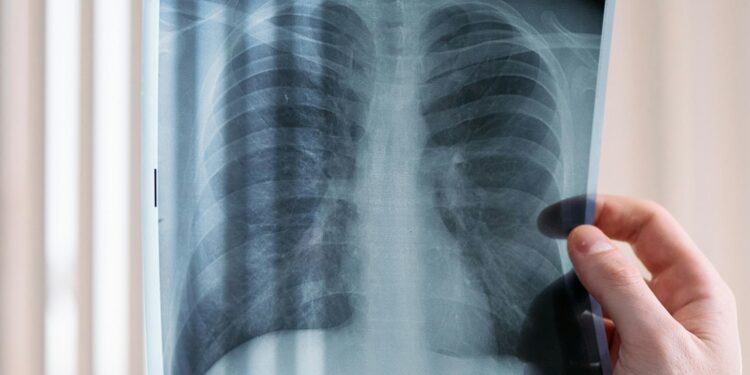

El Sistema de Salud de Guanajuato informó que en las unidades médicas se realizan pruebas para detectar a través de análisis de laboratorio, radiografía y valoración clínica si alguna persona puede padecer tuberculosis.